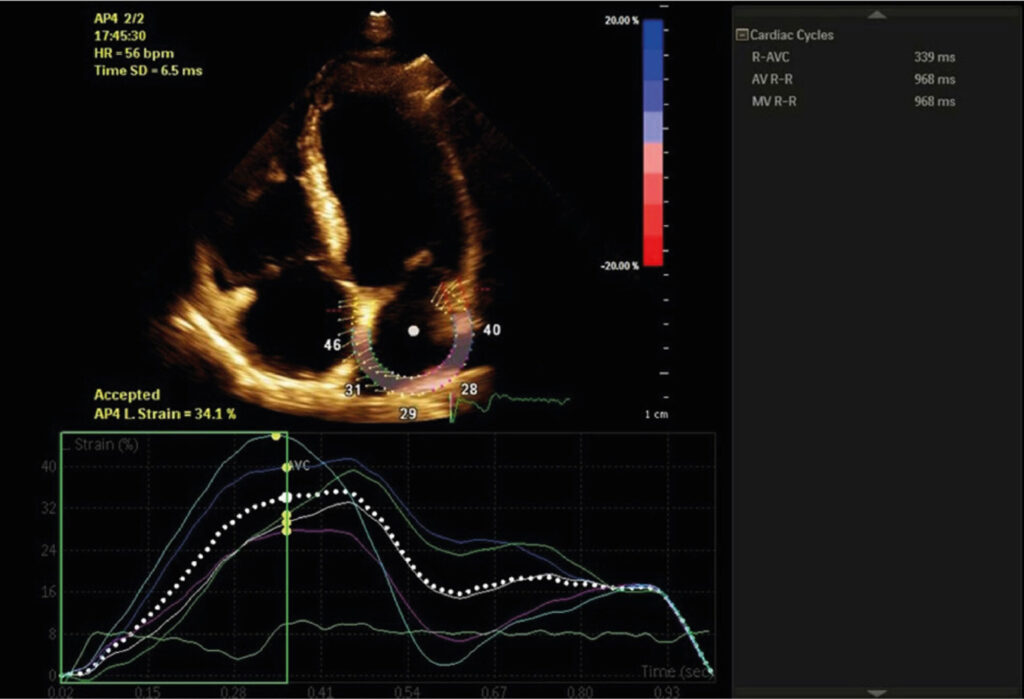

Observational study with individuals in sinus rhythm and preserved left ventricular ejection fraction, submitted to echocardiogram and divided into three groups according to the combined analysis of E/e´ ratio and indexed left atrium volume: Group 1, if normal left ventricular filling pressures; Group 2, if increased left ventricular filling pressures and Group 3, if indeterminate left ventricular filling pressures. Two-dimensional speckle tracking was used to measure peak left atrial strain (LAS). Analysis of variance, Student’s t test and receiver-operator curve (ROC) were used in the statistical analysis.

We included 58 patients who had 61 ± 14 years old, 57% of whom were women, and had average left ventricular ejection fraction 62 ± 7%. Groups 2 and 3 had lower LAS than Group 1 (20 ± 5% versus 22 ± 6% versus 30 ± 8%, respectively, p = 0.004), but did not differ between them (p = 0.93). LAS was a good predictor of elevated left ventricular filling pressures (p = 0.026; area under the curve = 0.80), obtaining sensitivity of 60% and specificity of 80% with a cut-off value ≤ 20%.

The findings suggest that the left atrial reservoir function of individuals with indeterminate diastolic function is similar to that of individuals with advanced diastolic dysfunction, rendering LAS the potential to support the reclassification of indeterminate diastolic function.